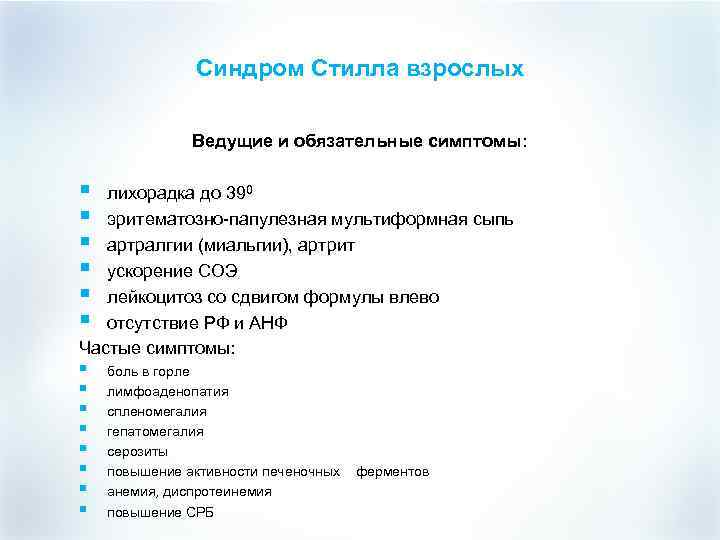

Синдром Стилла взрослых Ведущие и обязательные симптомы: § § § лихорадка до 390 эритематозно-папулезная мультиформная сыпь артралгии (миальгии), артрит ускорение СОЭ лейкоцитоз со сдвигом формулы влево отсутствие РФ и АНФ Частые симптомы: § § § § боль в горле лимфоаденопатия спленомегалия гепатомегалия серозиты повышение активности печеночных анемия, диспротеинемия повышение СРБ ферментов

Синдром Стилла взрослых Ведущие и обязательные симптомы: § § § лихорадка до 390 эритематозно-папулезная мультиформная сыпь артралгии (миальгии), артрит ускорение СОЭ лейкоцитоз со сдвигом формулы влево отсутствие РФ и АНФ Частые симптомы: § § § § боль в горле лимфоаденопатия спленомегалия гепатомегалия серозиты повышение активности печеночных анемия, диспротеинемия повышение СРБ ферментов